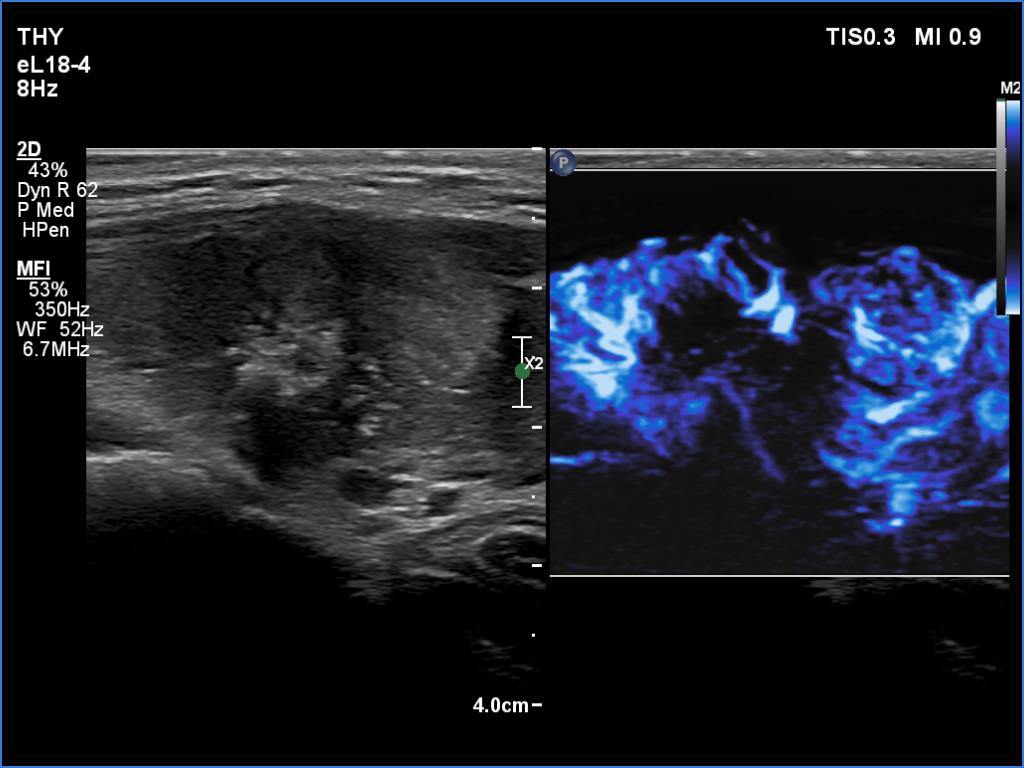

Right lobe, longitudinal scan

Right lobe, another longitudinal scan, microflow imaging. The central hyperechoic mass has no vessels.